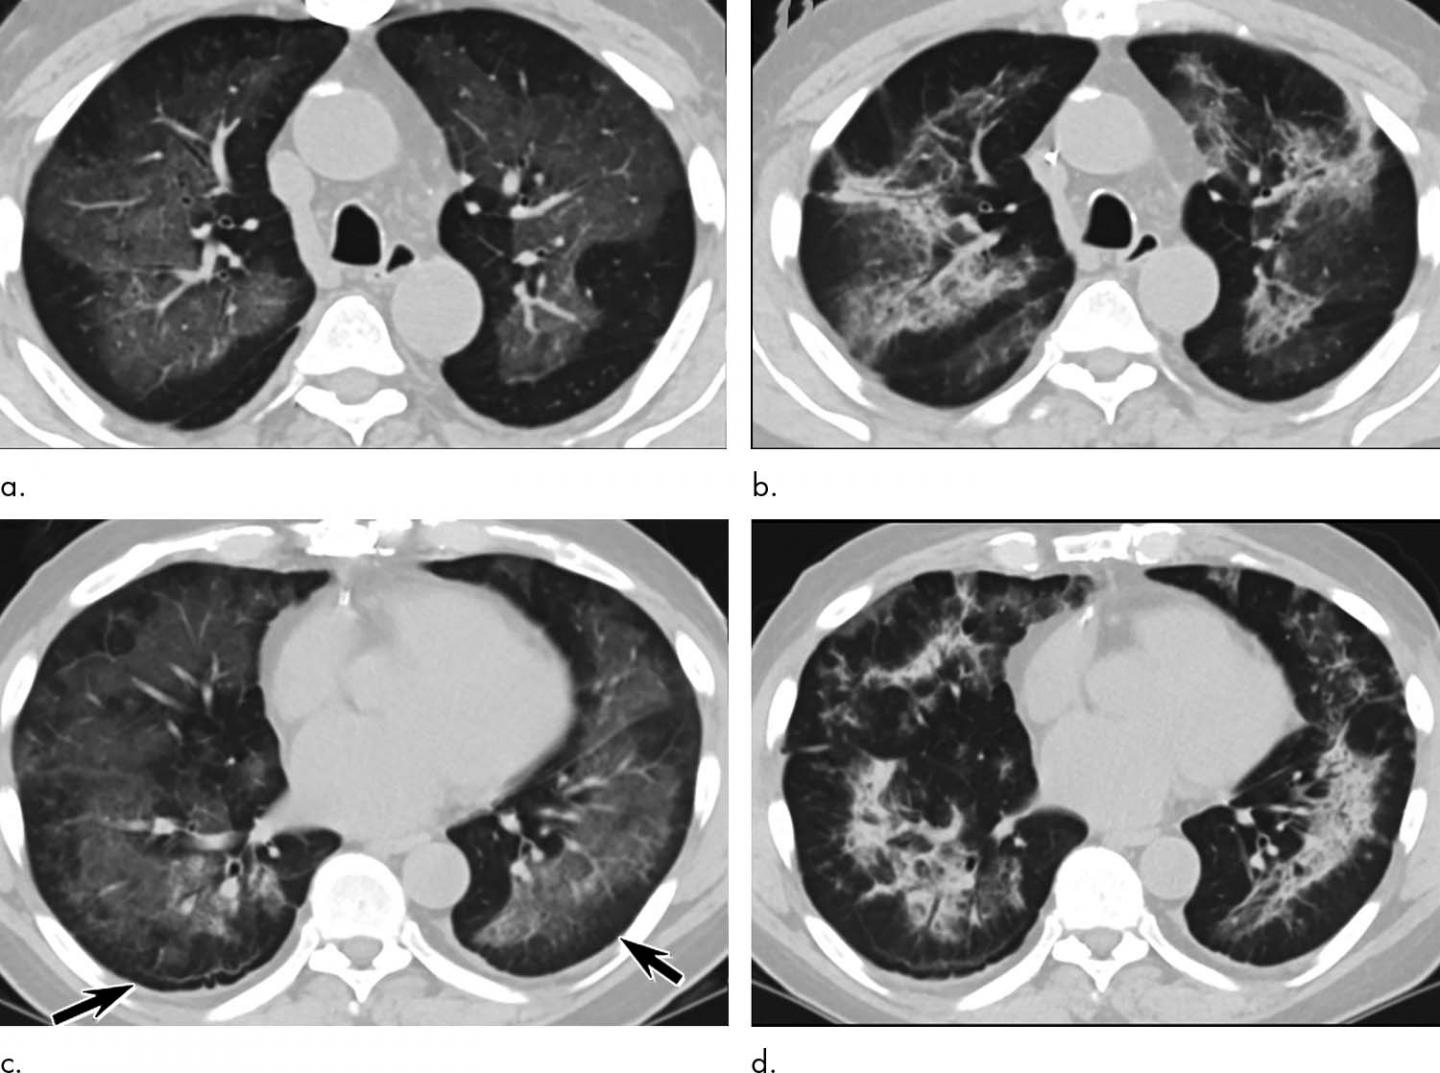

Diseases Free FullText Mosaic Pattern of Lung Attenuation on Chest Popcorn Lung On Ct On hrct chest, there are often sharply defined, areas of decreased lung attenuation associated with vessels of reduced calibre. Bronchiolitis obliterans is also known as obliterative bronchiolitis or constrictive bronchiolitis. Popcorn lung is a serious and irreversible condition in which the tiny air sacs in the lungs become scarred and constricted,. Bronchiolitis obliterans) is a rare condition in which lung. Popcorn Lung On Ct.